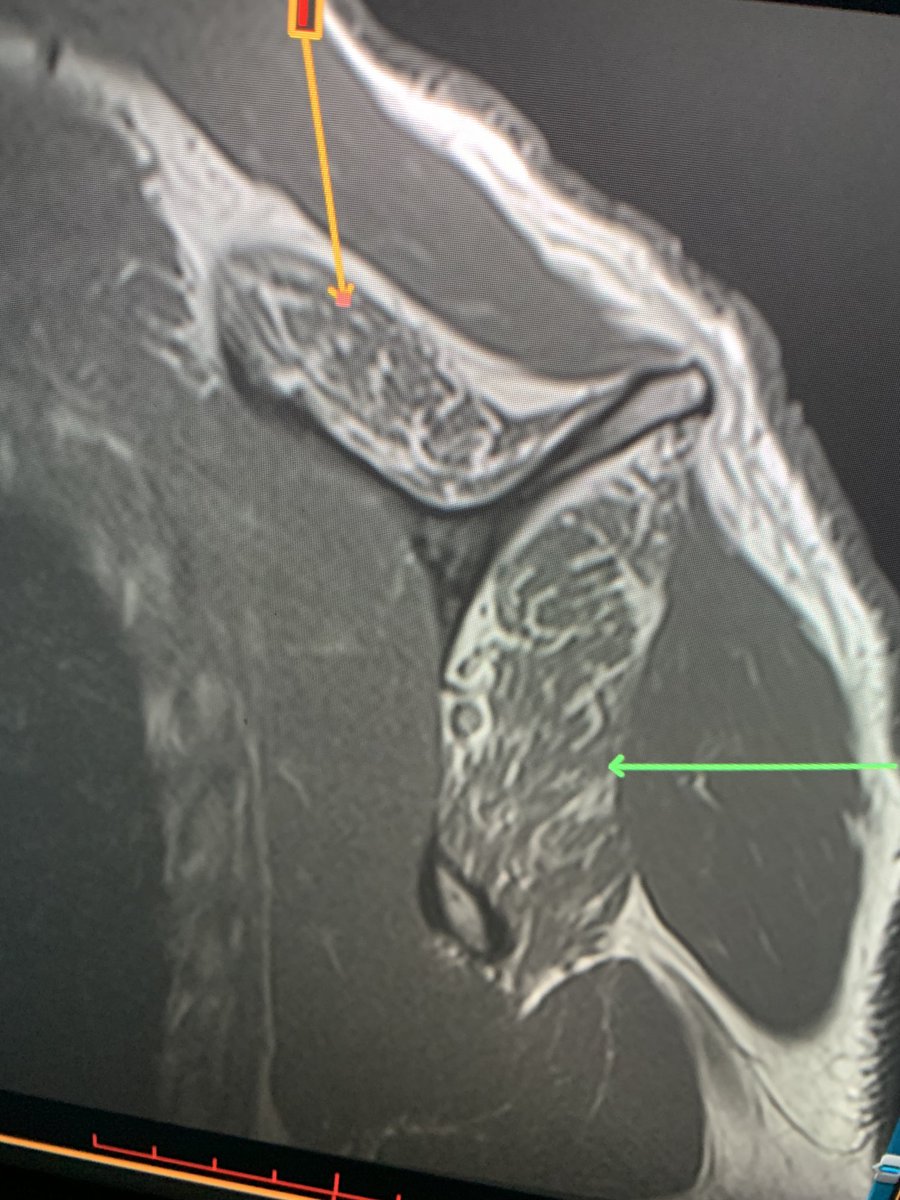

Young RHD pt in MVC with R shoulder dislocation and large cuff avulsion. Also w/ a DENSE brachial plexopathy with no motor or sensation below the deltoid. Axillary n. is ok. Everything distal to that is out. Plexus MRI shows edema w intact plexus Haven’t seen this in a bit